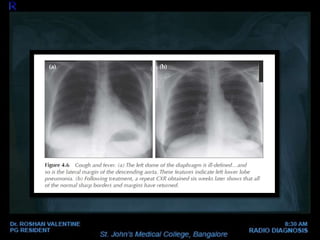

LOBAR CONSOLIDATION

where the affected portion

of the lung is expanded.